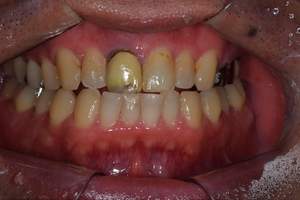

症例写真-1

- Befor

- After

| 年齢 | 50代・男性 |

| 主訴 | 右下歯が疼く |

| 治療内容 | ・右下6番インプラント ※1:FGG(遊離歯肉移植術)とは、足りない歯ぐきを上顎から上皮を切り取り移植する外科手術 |

| 治療費 | 合計:902,000円(税込) ■内訳 |

| 治療期間 | 9ヵ月 |

| 治療方針 | 右下の当該歯は歯根破折により保存不可能と診断しました。歯周疾患も伴っていたため抜歯後に骨吸収※1が大きく起こることが予測できました。チタンメッシュ併用骨再生誘導法(GBR※2)を選択しインプラント埋入と同時に行い自然な歯槽骨のラインを再現しました。またGBRを行う際にインプラント辺縁の付着歯肉の減少が起こる為、遊離歯肉移植術(FGG※3)を行い清掃性を考慮した形態に仕上げました。 ■治療方針の解説 治療した右下の歯をレントゲンで撮影したところ根本の部分に黒く写る箇所があり「根尖性慢性周囲炎※1」と診断。また歯周病も進行していました。 ※1 骨吸収・・・歯槽骨という歯を支える骨がなくなっていくこと |

| 担当者所見 | 主訴の右下だけでなく歯茎の腫れ、発赤があり不良補綴や不良充填など他にも治療箇所が多数ありました。プラークコントロールが不良であった為まずはブラッシング指導を行いセルフケアの重要性を理解していただくところからスタートしました。 右下6番の歯はインプラント治療を行なった結果審美的にも機能的にも患者様の満足を得ることができました。骨造成と歯肉移植も行なった為インプラントを支える十分な歯周組織の獲得ができたと思っております。 |